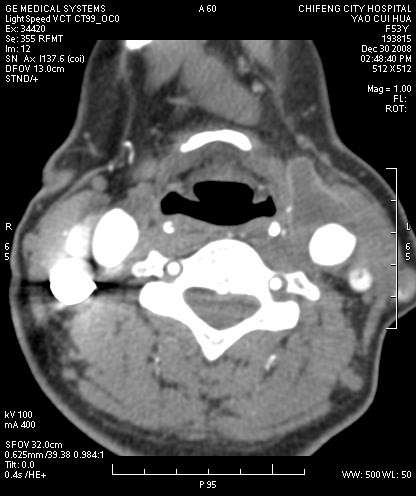

2009年元旦刚过血管外科收治了一个52岁的女性患者,左颈部可以触及乒乓球大小的搏动性包块。经过B超及头颈部CTA检查确诊为:颈总动脉瘤瘤腔内大量附壁血栓形成。病人随时有血栓脱落导致脑栓塞的可能。经过血管外科全科会诊,决定手术切除动脉瘤取出血栓,摘除这颗随时威胁到比如生命的炸弹。赤峰市医院血管外科党永康

3日经过麻醉科张希哲主任,梁晓东副主任医师的会诊顺利实行手术,为确保病人手术中脑部安全决定行颈丛神经阻滞,并给与手术中颈动脉测压防止意外发生。9时手术开始,顺利切开颈总动脉瘤取出3×1.5cm血栓,植入直径8mm长约5cm的德国贝朗人造血管。病人术中神情语利,无肢瘫,手术取得圆满成功。